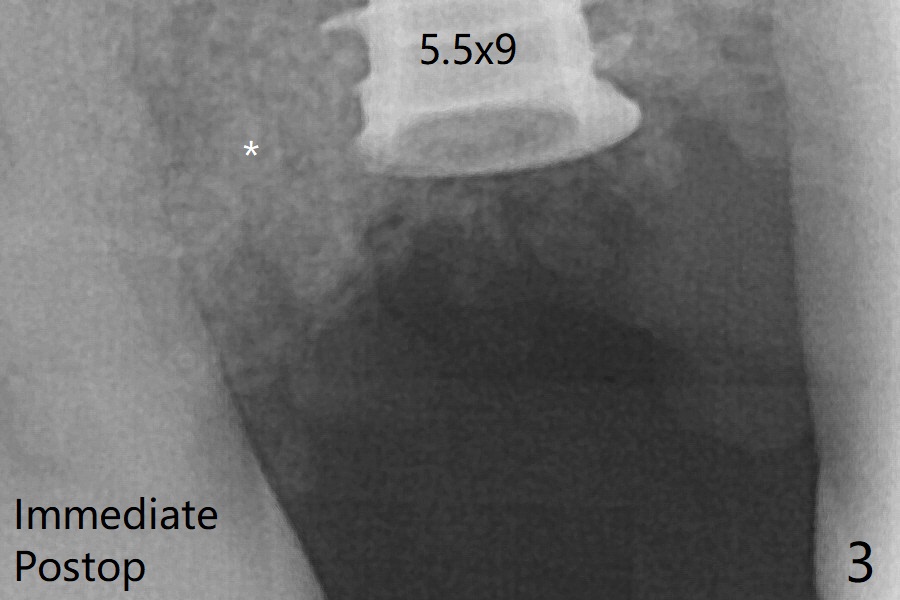

The bone graft (Fig.3 *) appears to have attached to the root of the neighboring tooth and the implant threads 7 months post op (COVID 19, Fig.5 arrowheads)).